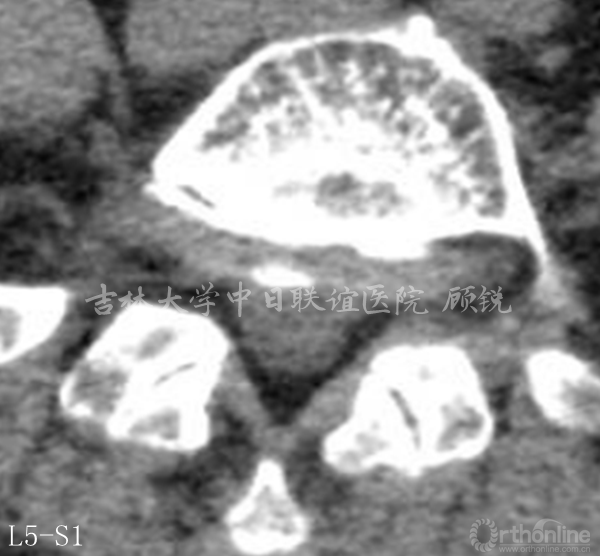

诊断为:L5峡部裂型滑脱(真性滑脱)(Ⅱ度),腰椎MRI平扫发现异常信号。

滑脱椎体后方椎管内见异常信号,是游离髓核(硬膜内)?椎管内肿瘤(神经源性、转移)?血管畸形?还是其他其他?组内会诊认为以疾病一元论解释患者的症状、体征考虑因滑脱椎导致马尾神经冗余的可能性大。进一步检查了增强腰椎MRI。

占位组织强化明显为实质病变,依据瘤体与硬膜间呈锐角;T1W1:等信号;T2W1:混杂高信号STIR:环状增强,Non-enhancement area(+)。经科内会诊该患者的诊断为:峡部裂型腰椎滑脱(L5 Ⅱ度)、腰椎管内占位性病变(神经鞘瘤?)。Ozawa H, Aizawa T, Kanno H.Epidemiology of surgically treated primary spinal cord tumors in Miyagi, Japan.Neuroepidemiology. 2013;41(3-4):156-60